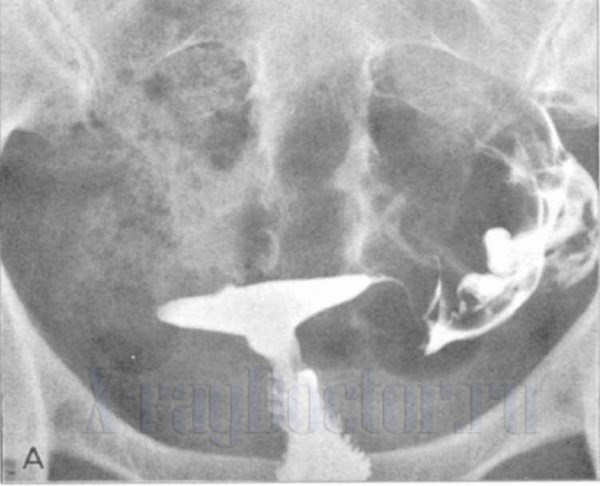

Для исключения других сопутствующих недугов прибегают к анализам крови и бактериологическим тестам. Показателен также и рентген с контрастом. Он проводится с использованием специальных средств, вводимых в мочевой пузырь через уретру. С его помощью получаются своеобразные фото, которые также помогают в определении локализации. В ряде случаев требуется проведение эндоскопического исследования влагалища, а также осуществляется компьютерная томография.